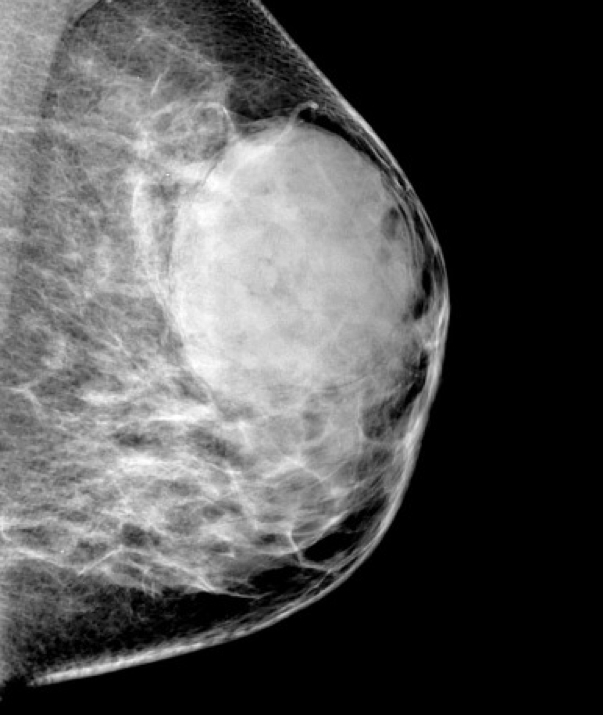

Phyllodes Tumour (Giant Fibroadenoma)

- Similar origin to fibroadenoma: benign tumour of intralobular stroma with glandular elements

- Common in older women (50–60 years)

- Capsulated, firm, grey nodular mass

- Distinguished by “phyllodes” (leaf-like) clefts and slits

Clinical Features

- Typically benign but locally aggressive

- May recur without excision

- Can be premalignant, especially in older patients

- Expanding lesion without nipple retraction

- Metastasis is rare

- Surgical excision recommended to prevent recurrence

2. Credit: https://radiopaedia.org/articles/giant-fibroadenoma